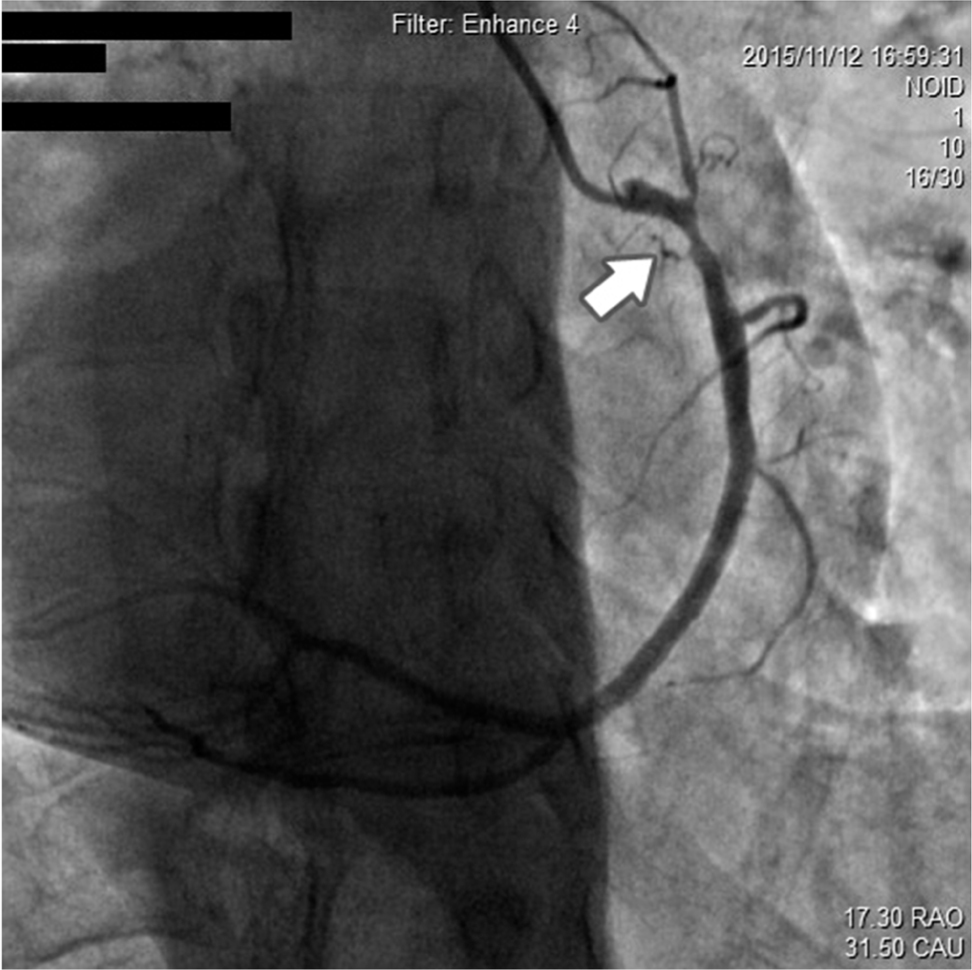

Regarding angiographic findings, no hemodynamically significant stenosis of left anterior descending artery (LAD), left main coronary artery (LM), left circumflex artery (LCX), and antegrade TIMI III flow was found ( Fig. 2). The RCA, as a dominant vessel, was thick with 80% diameter stenosis ( Fig. 3). Assuming this site to be the cause of discomfort, we proceeded with surgical intervention to open the occluded RCA. After balloon pre-dilatation, a Xience V® 3.0 × 23 mm (Abbott Vascular, Santa Clara, CA, USA) drug-eluting stent was subsequently implanted at the lesion site (Fig.4A), using an inflation pressure of 16 atm for 20s. The intervention was successful, achieving optimal antegrade TIMI III flow without residual stenosis (Fig. 4B). The patient’s recovery post-angioplasty was uneventful.

RCA showing nearly 80% of proximal segment stenosis.